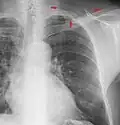

A chest radiograph showing bronchopulmonary dysplasia. -